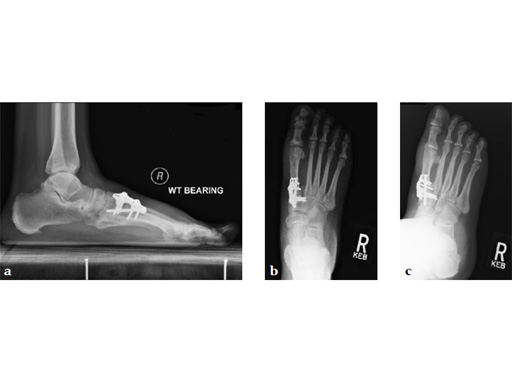

Case 3: First TMT fusion plate

A 48-year-old woman, with hallus valgus and hypermobile medial column, also resulting in pes plano abductovalgus (flatfoot).

Case provided by Andrew Sands, New York, New York, USA

Surgery consisted of first TMT and intertarsal corrective osteotomy plus fusion with movement of the first MT lateral and plantar. This corrects the hallus valgus as well as the PPAV (and stabilizes the medial column).